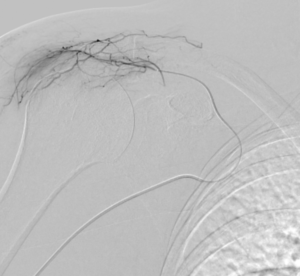

L’embolisation de la capsulite rétractile est une innovation récente qui cible la cause profonde de l’inflammation : l’hypervascularisation. Dans une épaule gelée, de petites artères anormales se développent autour de la capsule, alimentant le processus inflammatoire et la douleur.

Grâce à l’imagerie de précision (angiographie), le radiologue interventionnel identifie ces vaisseaux « anormaux » et les occlut sélectivement. En bloquant leur flux sanguin, on réduit l’apport en oxygène et nutriments à la zone enflammée, favorisant une résolution rapide des symptômes.

- Guidage par imagerie : Le cathéter est avancé jusqu’à l’artère sous-clavière sous contrôle radioscopique en temps réel.

- Injection ciblée : Lipiodol dilué dans du produit de contraste iodé est injecté pour boucher les artères pathologiques.

- Vérification : Angiographie de contrôle pour confirmer le succès.